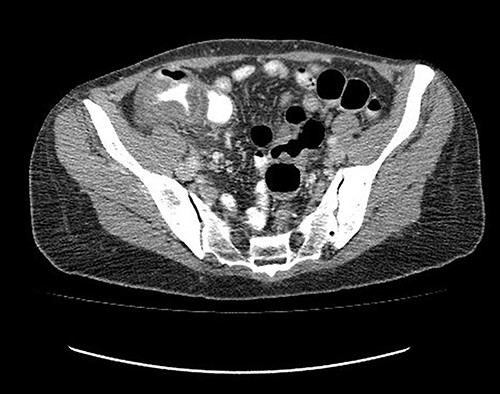

Analgesic management was prescribed, blood chemistry and thorax and abdomen X-ray were performed without abnormal results. An abdominal CT was performed, which showed concentric, focal thickening of the cecal walls, with a maximum thickness of 30 mm in the lateral wall, with enhancement with contrast, without evidence of pneumoperitoneum (Fig. 2). Given the history of recent polypectomy, patient’s symptoms, and the absence of signs of intestinal perforation, the diagnosis of PPS was made. Bowel rest, parenteral fluids and antibiotics (third-generation cephalosporin) were indicated, with a full recovery. The patient was discharged 24 h after admission. She was later evaluated in the coloproctology outpatient clinic, with complete resolution of symptoms. The histopathological study of the resected polyp was described as a hairy tubular adenoma. She was scheduled for a 1-year follow-up consult with a new colonoscopy study.

Abdominal tomography without pneumoperitoneum and with thickening of the concentric intestinal wall, without signs of intestinal perforation.